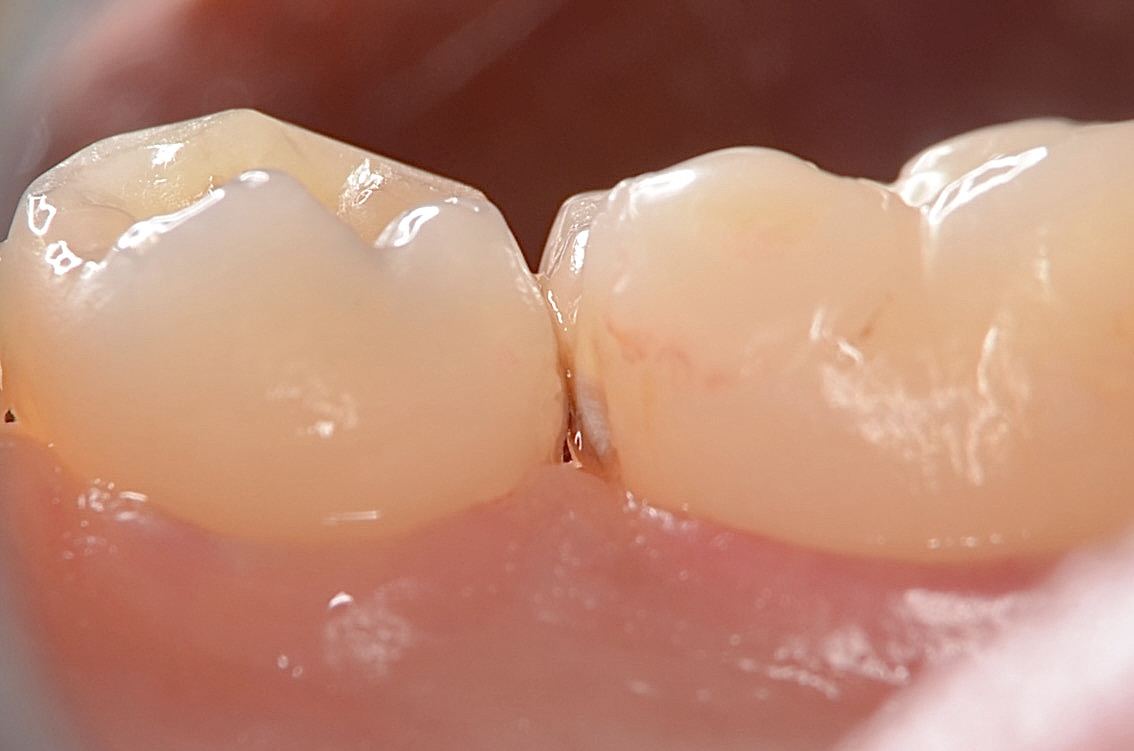

6番近心舌側の隣接面

茶色くなっている虫歯が見えます -